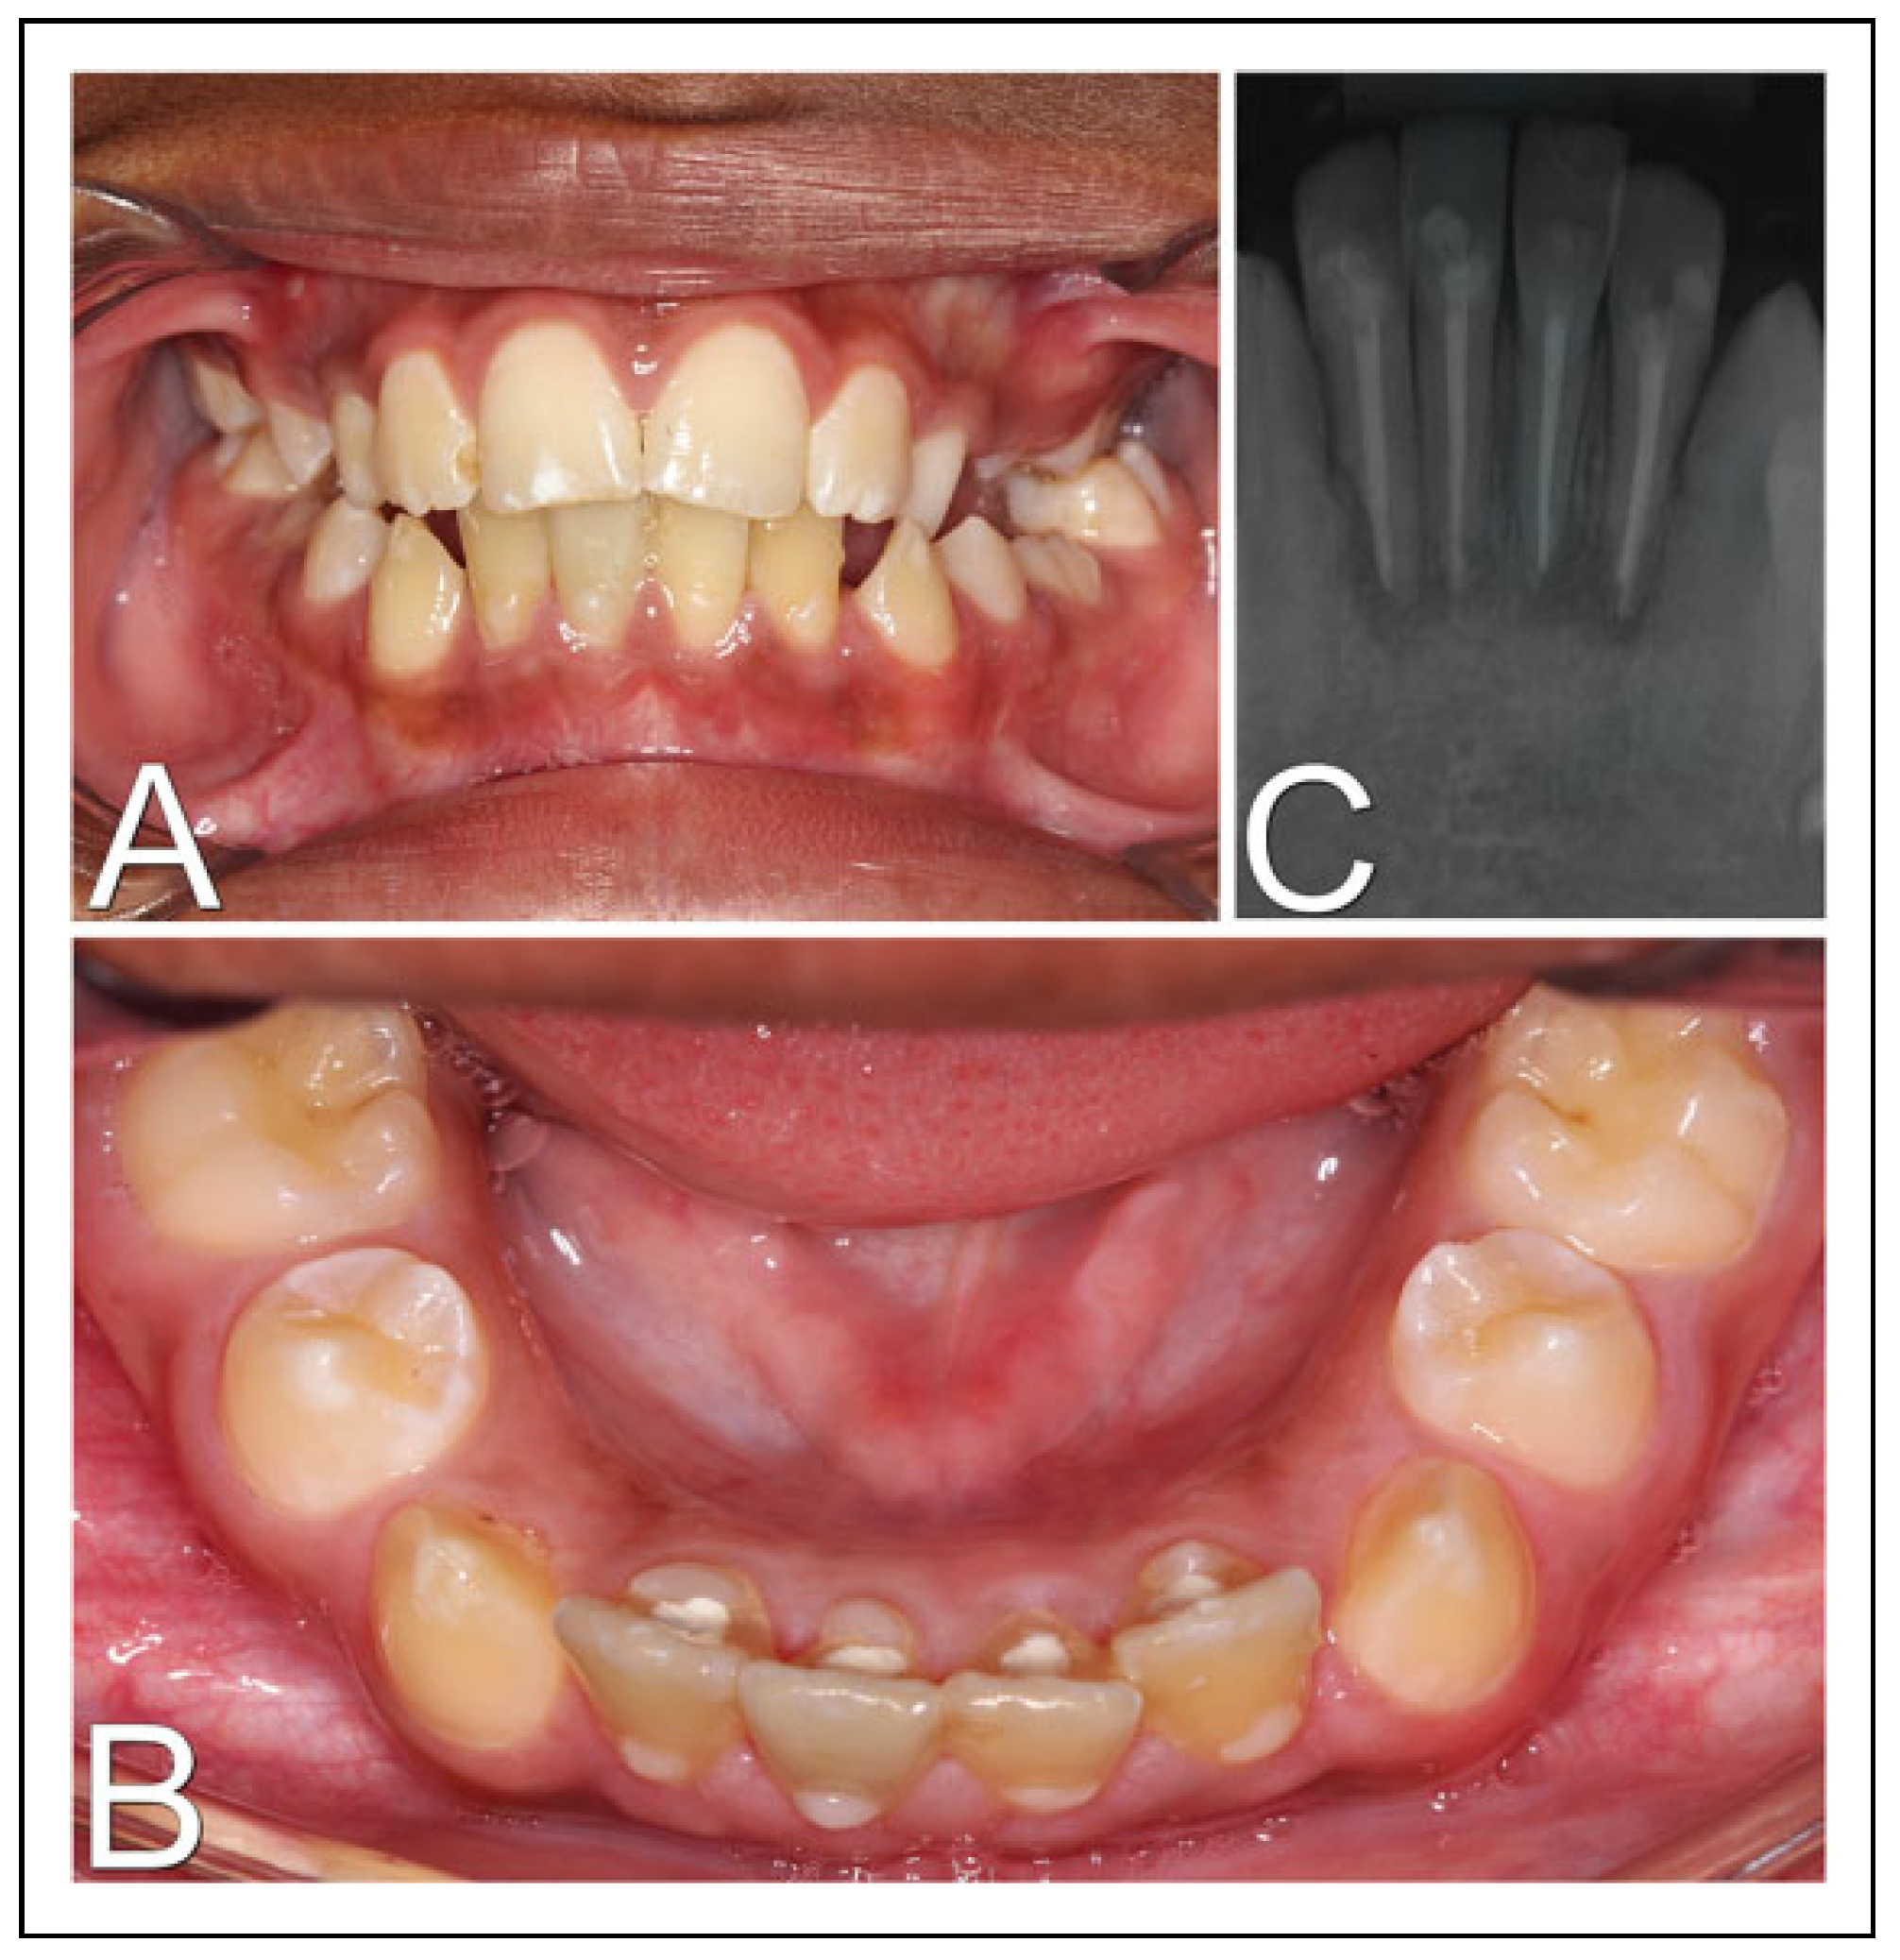

A 10-year-old male and systemically healthy patient received emergency care at the hospital, for having fallen from his own level. In the intraoral examination, bleeding, gingival laceration, severe mobility and lingual displacement of the lower incisors were found, with exposure of the dental apexes and severe pain complaints. The fractured block was only attached to the lingual gingival tissue (Figure 1A). In a tomographic evaluation, it was possible to observe an alveolar process fracture of the lower incisors (Figure 1B and C). In emergency care, with local anesthesia, the wounds were sutured and the dentoalveolar fragment was repositioned with semi-rigid dental splinting (Figure 1D). The patient had mixed dentition and the lower canines were not erupted, which prevented adequate stability. Therefore, another surgical procedure was planned under general anesthesia. Informed and valid consent was obtained from the legal guardian for the patient.

Figure 1. Initial exams and procedures. (A) Intraoral image in front view; (B) computed tomography in sagittal section confirming dentoalveolar fracture; (C) 3-dimensional reconstruction of computed tomography; (D) intraoral image after wound sutures and semi-rigid dental splinting.

Figure 5. Nine-month follow-up. (A) Intraoral photograph in front view; (B) intraoral photograph in upper view; (C) periapical radiography after endodontic treatment finalization, with signs of periapical bone rarefaction.